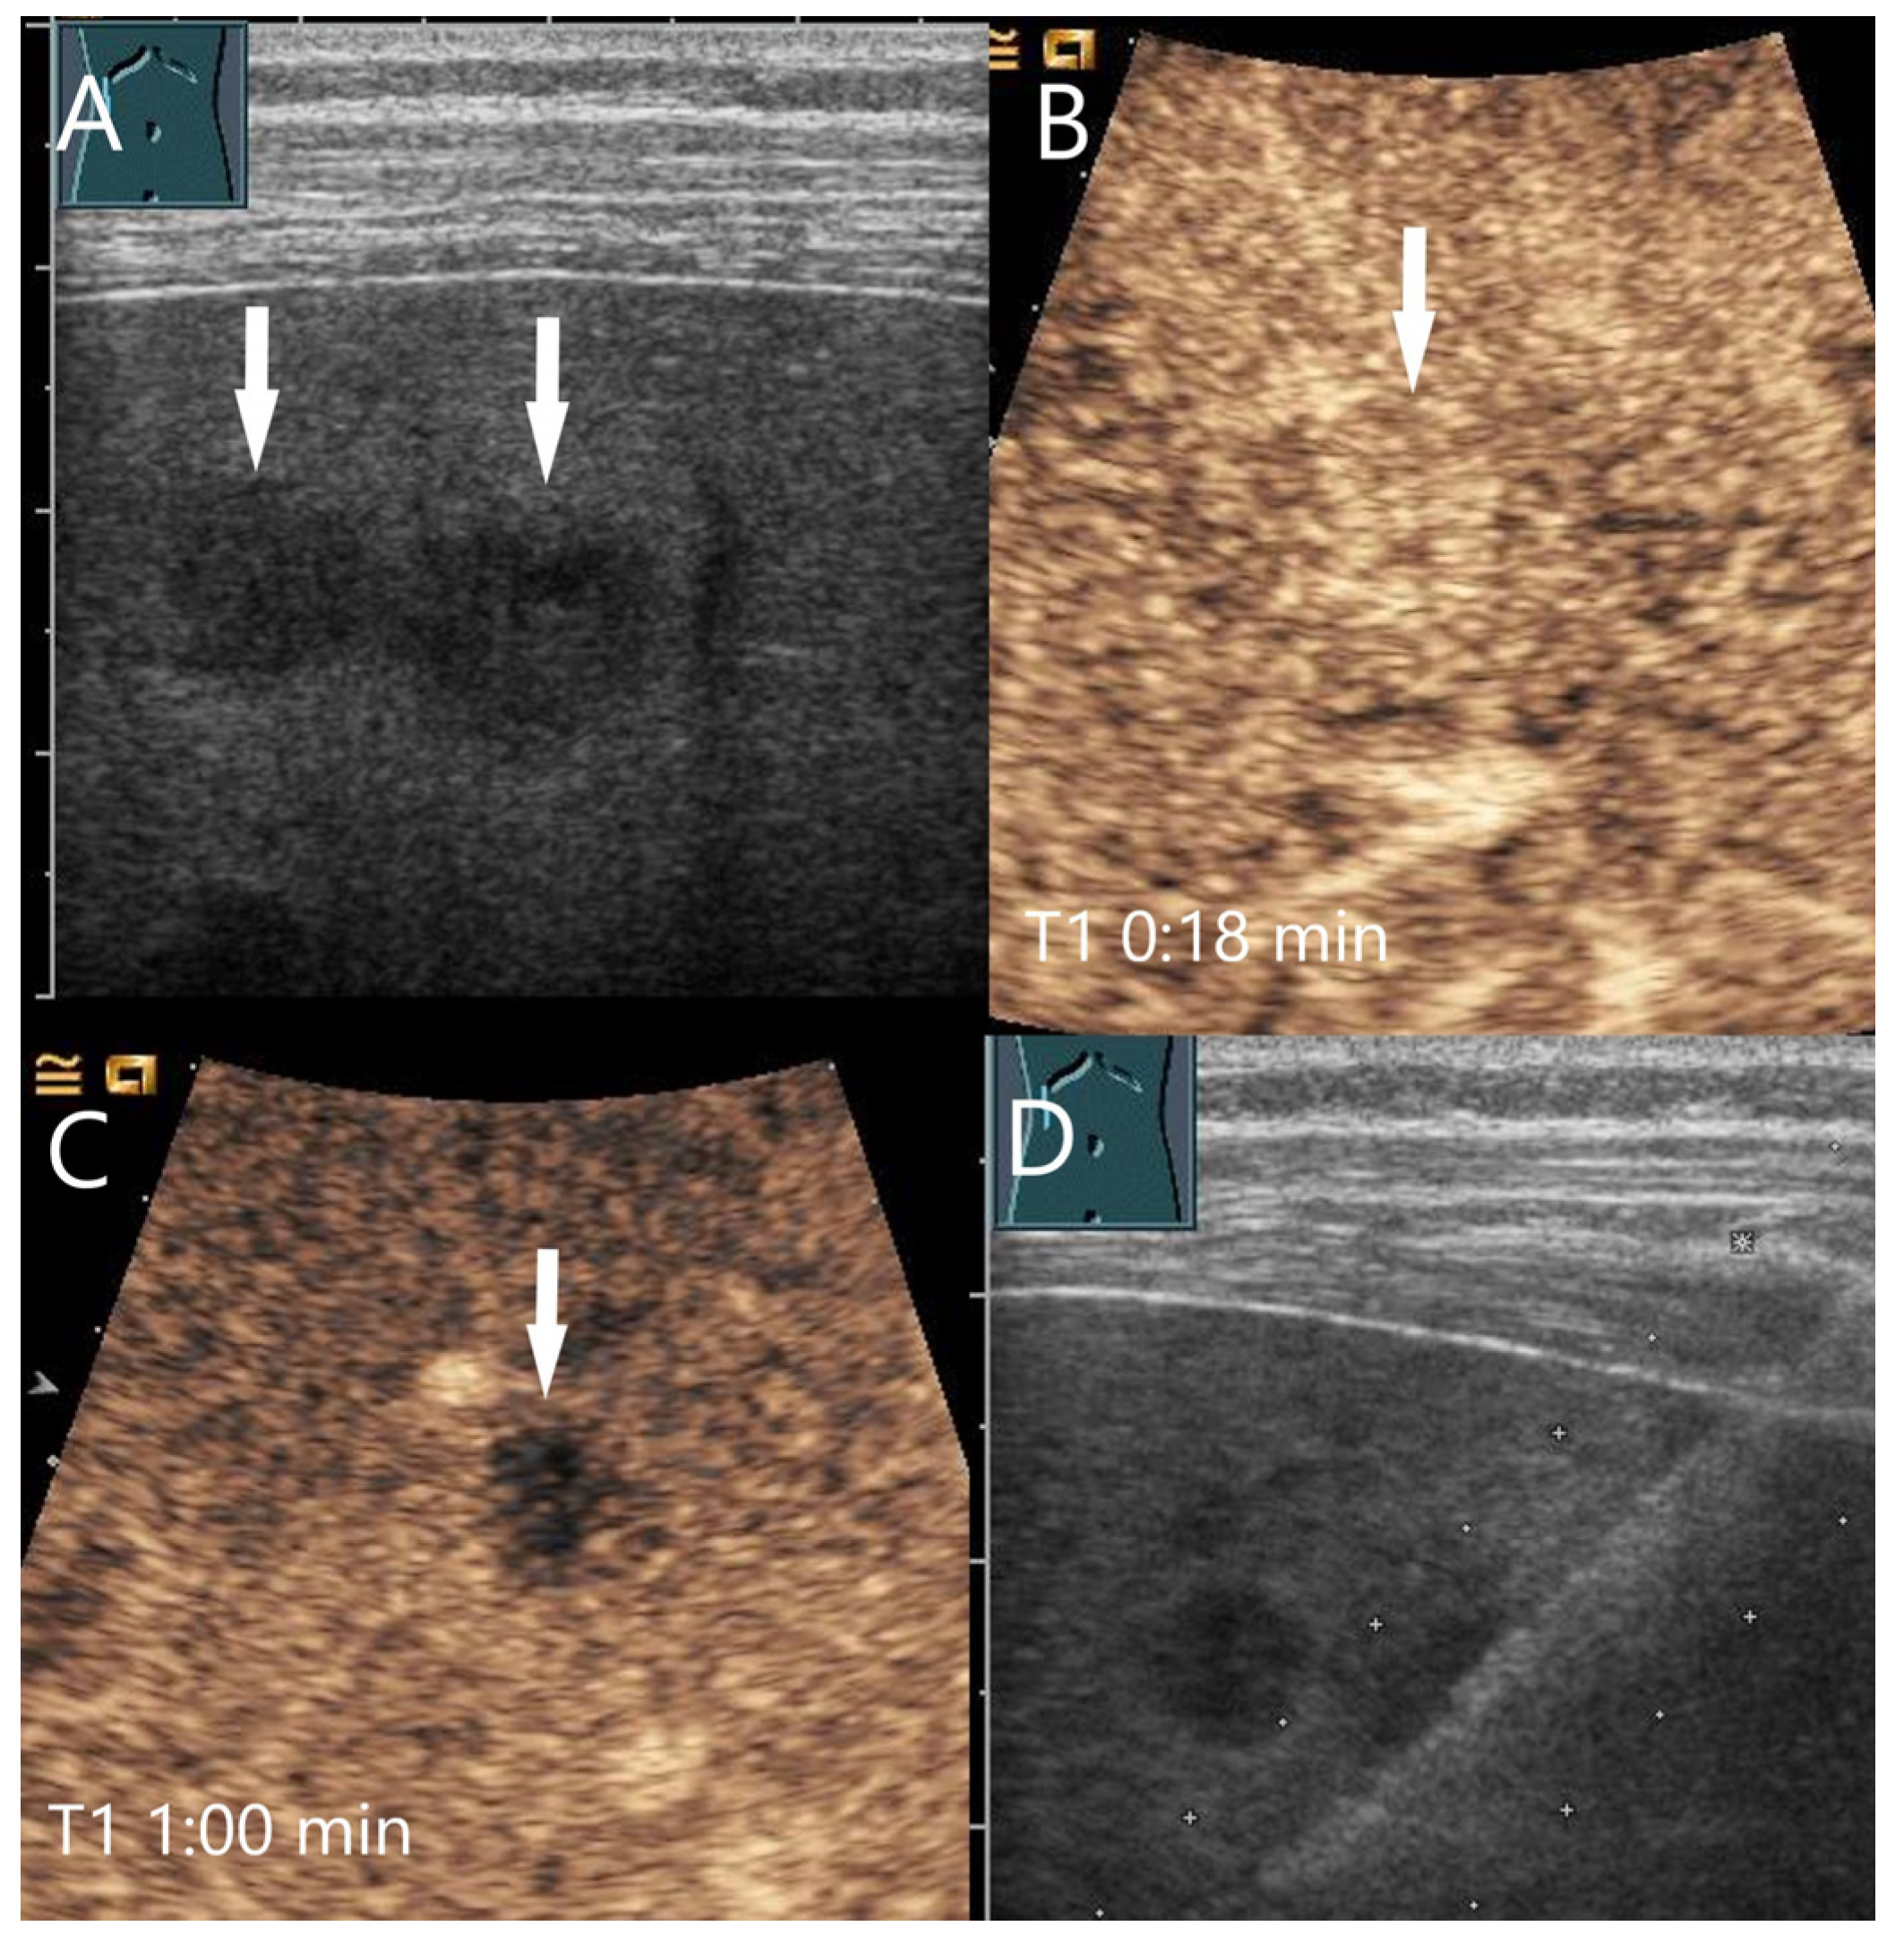

IgG4-associated inflammatory pseudotumor. In a patient with elevated liver enzymes and alcohol abuse, B-mode US showed steatosis hepatis and a 55 × 20 mm irregular oval hypoechoic lesion (A). The central tubular structure was without flow evidence on CDI, and we interpreted this as a small bile duct branch. On CEUS, the lesion (arrows) was homogeneously hyperenhanced in the AP (B). In the PVP, a mild hypoenhancement developed (C), which became more pronounced in the LP (D).

Figure 17.

IgG4-associated inflammatory pseudotumor. Male patient with pain in the right upper abdomen. The B-mode US shows a hypoechoic wall around the portal veins in the center of the hepatic hilus (A). CEUS shows a slight arterial hypoenhancement after 27 s (B) with clear parenchymal washout after 1 min in the PVP (C). This irregularly delimited area had a size of about 60 × 50 mm. The US-guided biopsy (D) was diagnostic for IgG4 positive chronic sclerosing lymphoplasmacytic inflammation.